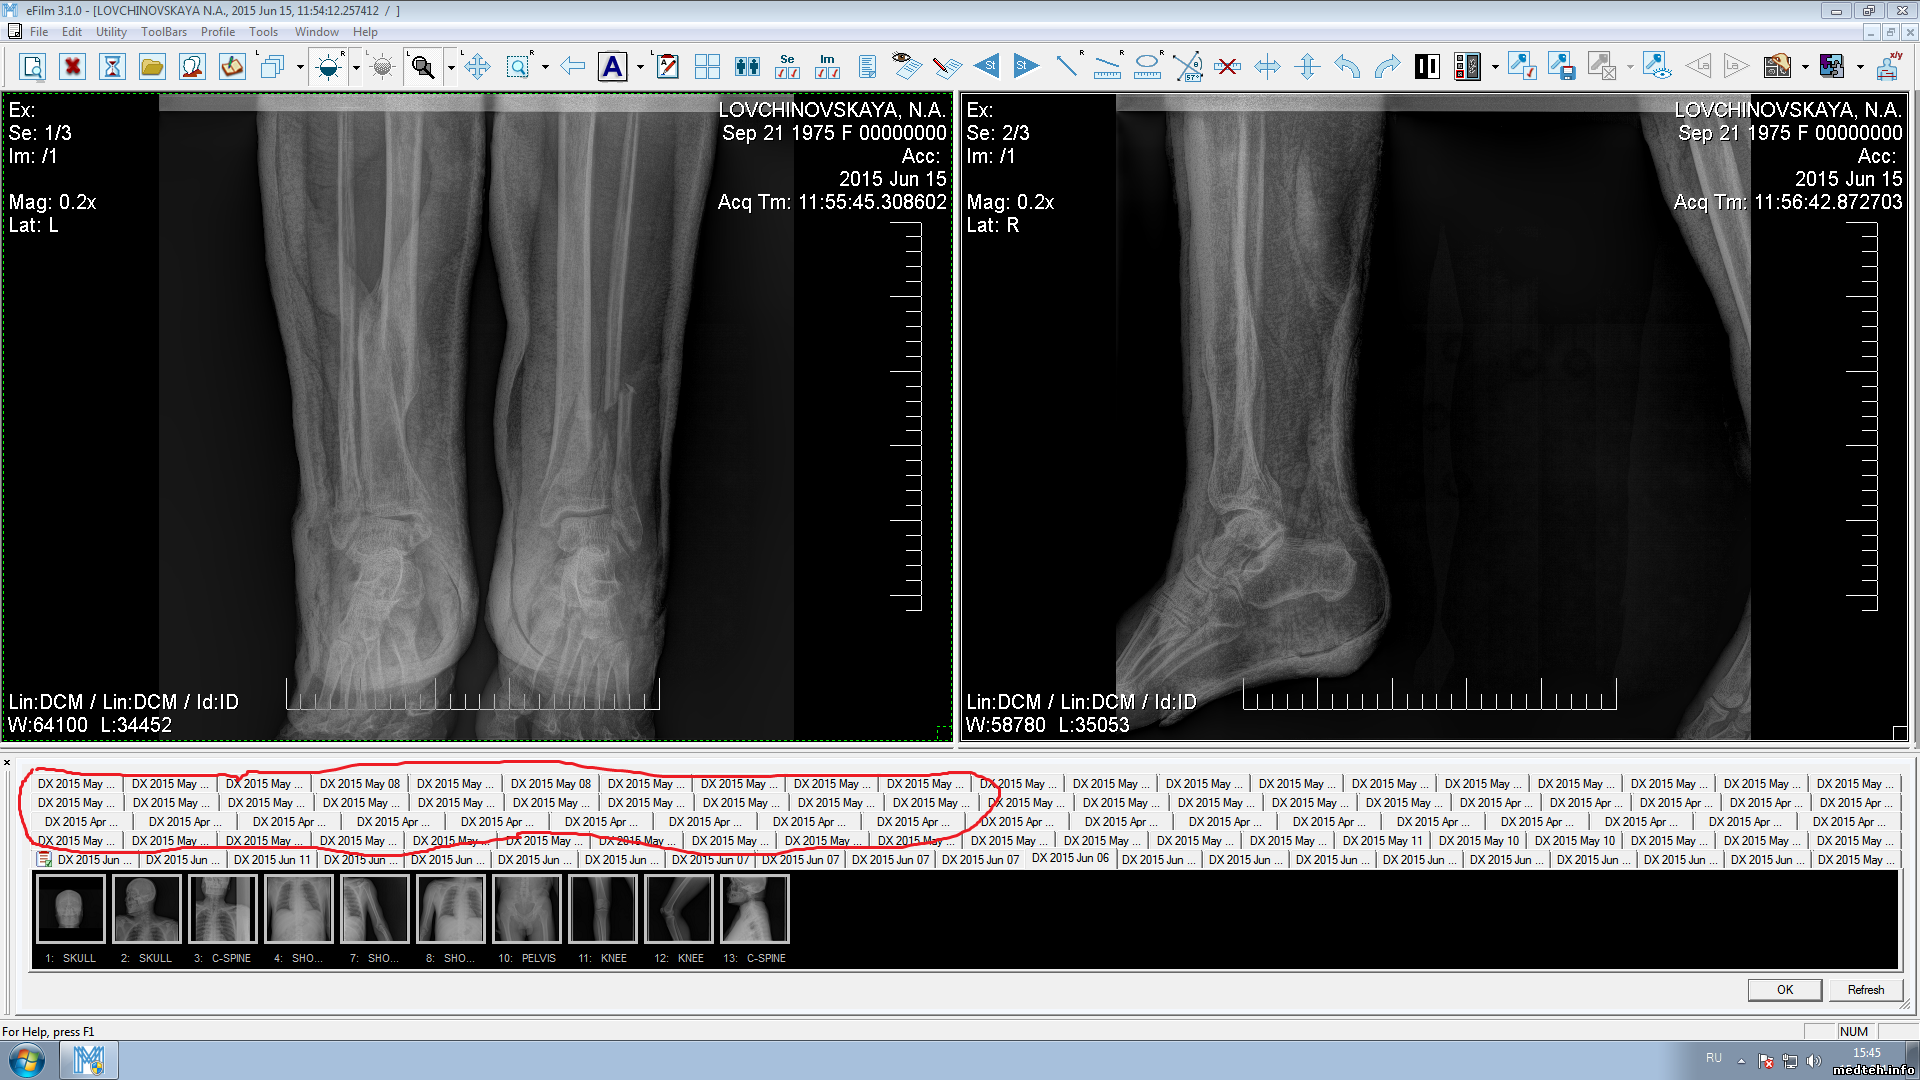

Апр 2015